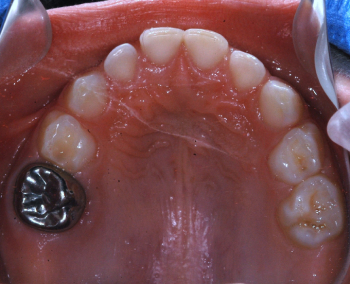

Odontopediatría

Caso 1